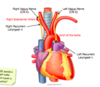

Phrenic nerve passes ______ and the vagus nerve passes ______ to the hilum of the lung.

Phernic nerve passes anterior and the vagus nerve passes posterior to the hilum of the lung.

Describe the coarse of the vagus through the thorax and what branches it gives off to the larynx

What do these branches do, what type of fibres does it carry?

On which side would a hilar lymph node cause a hoarse voice?

What pathology could cause a hoarse voice on the other side?

The vagus nerve travels from the brainstem down into the thorax, posterior to the hilum of the lung.

The right vagus gives off the right recurrent laryngeal nerve at the level of the right subclavian artery.

The left vagus nerve gives off the left recurrent laryngeal nerve at the level of the aorta, it arches back up to reach the larynx.

The recurrent laryngeal nerve innervates all the muscles of the larynx except cricothyroid and does all the sensory innervation below the vocal folds. A pancoast tumour could compress the R RLN.

A hilar lymph node could cause a hoarse voice on the left side, swelling of the lymph node at the hilum could compress the left recurrent laryngeal nerve as it passes under the arch of the aorta.